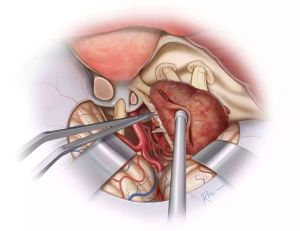

CCF的治療目的(1)保護視力;(2)消除雜音;(3)使眼球回縮;(4)防止腦缺血或出血。由於CCF的臨床症狀呈進行性加重,因此,必須採取有效的措施進行治療,以減少動脈血液流入海綿竇。但由於瘺的供血是多途徑的,故對本病的治療仍然是一個艱巨的任務。20世紀70年代以前外科治療大體分3個階段:第一階段(19世紀初~1930年):結紮患側頸動脈,有效率30%~40%,缺血加重且易復發;第二階段(1931~1960年):孤立術。先結紮頸部動脈,繼之開顱夾閉床突上段,有效率56.9%;第三階段:放風箏填塞;開顱借穿刺針導入銅絲、馬尾;個別報導開顱行直視下修補手術。但由於開顱手術的繁瑣和導致併發症後給病人帶來的痛苦,以及難以達到理想的治療效果或解剖治癒,所以有條件的醫院目前比較普遍的是採用血管內治療。

患者,男,31歲,因車禍致頭痛並右側 鼻腔流血水3h入院。診斷為雙側額葉腦挫傷、 顱底骨折。給予 神經外科常規治療, 鼻腔漏液顏色逐漸變淡,且時斷時續。入院後第13天右側 鼻腔突然出現暴發性 鼻出血,請耳鼻喉科給予右側後鼻腔填塞,止血效果滿意。第15 天行全腦血管 造影確診為右側頸內動脈海綿竇瘺合併右側頸內動脈、眼動脈瘤。經對症處理,作好Mata訓練後於第18 天行介入治療。穿刺右側股動脈置5F鞘,行全腦血管 造影示右側頸內動脈海綿竇瘺,右側頸內動脈眼動脈瘤。穿刺左側股動脈置8F鞘,置8F導引導管於右側頸內動脈,經導引導管置不可脫 球囊閉塞右側頸內動脈,同時行左側頸內 動脈造影,示右側 大腦半球側支循環良好。經 造影管置5cm×8mm 彈簧圈於右側頸內及頸外動脈起始處,計10枚,造影示血流減少,緩慢。拔除雙側股動脈鞘,加壓包紮。